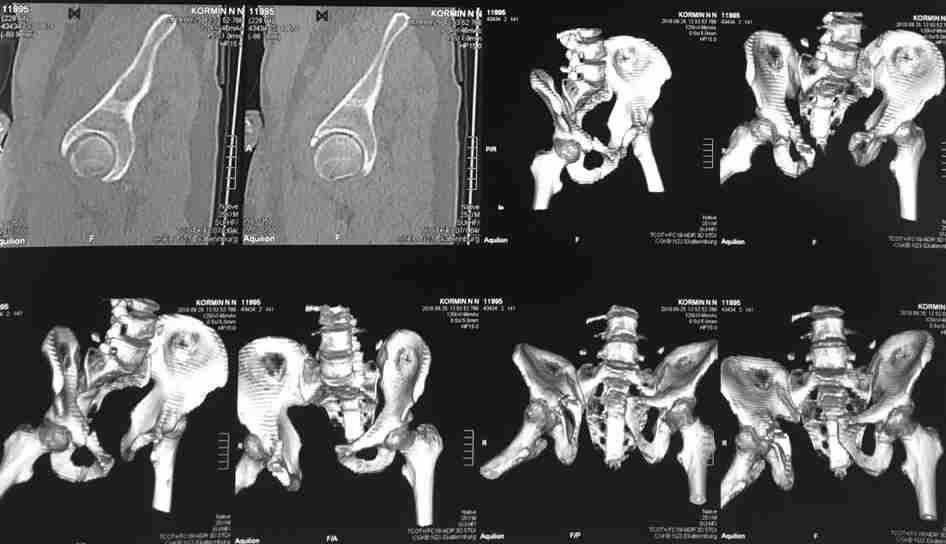

Коллеги, как и когда вы бы разрешили нагрузку в такой ситуации.

Молодой парень, без соматики. Сейчас чуть больше 2-х нед после операции,

швы сняты, мочится сам. Был тяжелый, после операции дней 10 пытался

выполнить лежа поперечный шпагат (успешно, так и лежал большей частью,

может быть из-за обширной гематомы промежности). Репозиция не

идеальная, но фиксация довольно надежная, за 2 нед ничего не

разъехалось". Сейчас пришел в ум. Когда, по-вашему, можно дать нагрузку,

и на какую ногу, или на обе? Или вообще подскажете

программу реабилитации.

PS Заранее извиняюсь за качество снимков, до не делали (body scan),

если не видно - то - полные разрывы КПС с двух сторон. после КТ

сломался. Неврологии вроде бы нет.